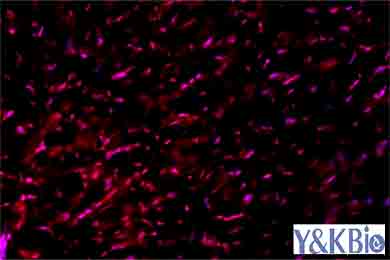

新疆Masson染色是病理染色服务中比较常见的一种,Masson染色用于胶原纤维和肌纤维的染色及鉴定;染色结果:胶原纤维呈蓝色、肌纤维呈红色、细胞核呈蓝黑色。